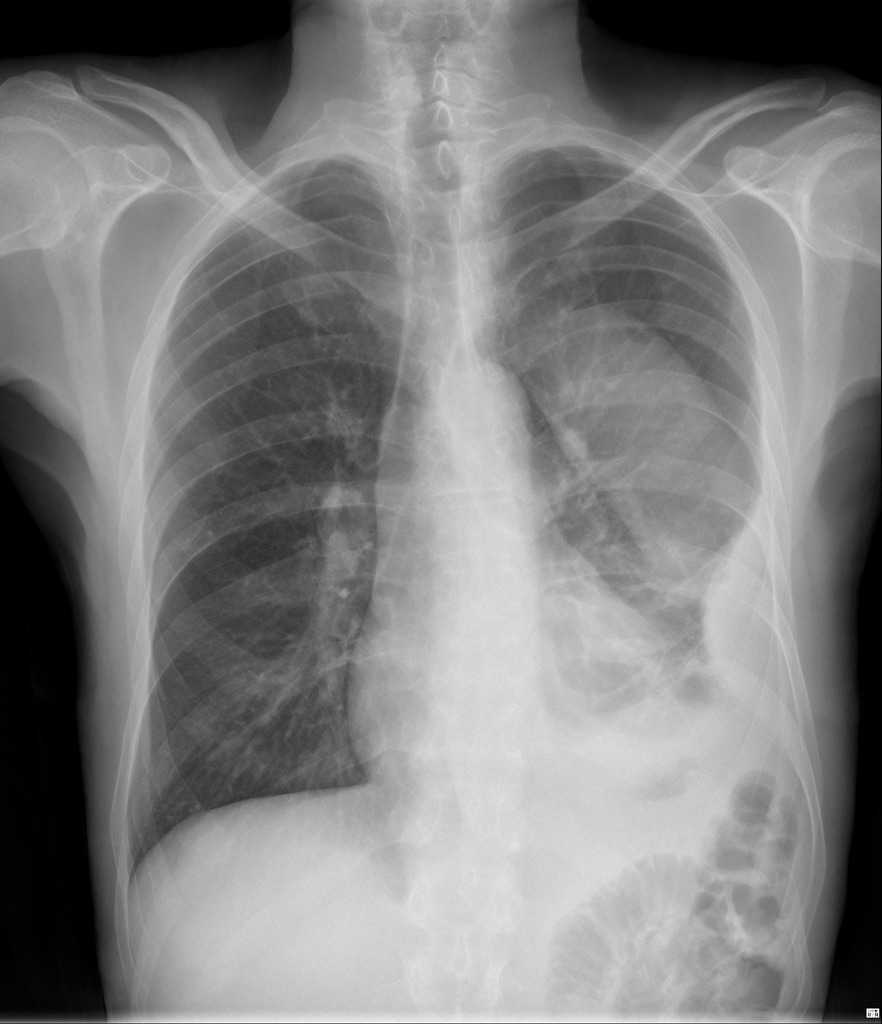

- Рентген ОГК. Для анасарки характерно повышение кардиоторакального индекса (>50%). Транссудат в плевральной полости диагностируют по поджатым легким, обрезанным синусам.

Плевральный выпот может быть выявлен на обзорной рентгенограмме органов грудной клетки. Эмпиему следует подозревать у пациентов, организм которых не отвечает на соответствующую антибактериальную терапию.

Ультразвуковое сканирование является предпочтительным методом исследования. Оно дает возможность точно определить местонахождение любого скопления жидкости и помогает наметить точку для проведения диагностической аспирации. Иногда плевральная инфекция возникает из-за разрыва пищевода. Этот диагноз следует подозревать у пациентов, у которых развивается плевральный выпот вскоре после многократной рвоты. При обнаружении патологического сброса из пищевода (применяется рентгеноскопия с контрастным веществом) необходимо незамедлительно направить больного к хирургу, имеющему опыт лечения разрывов пищевода.